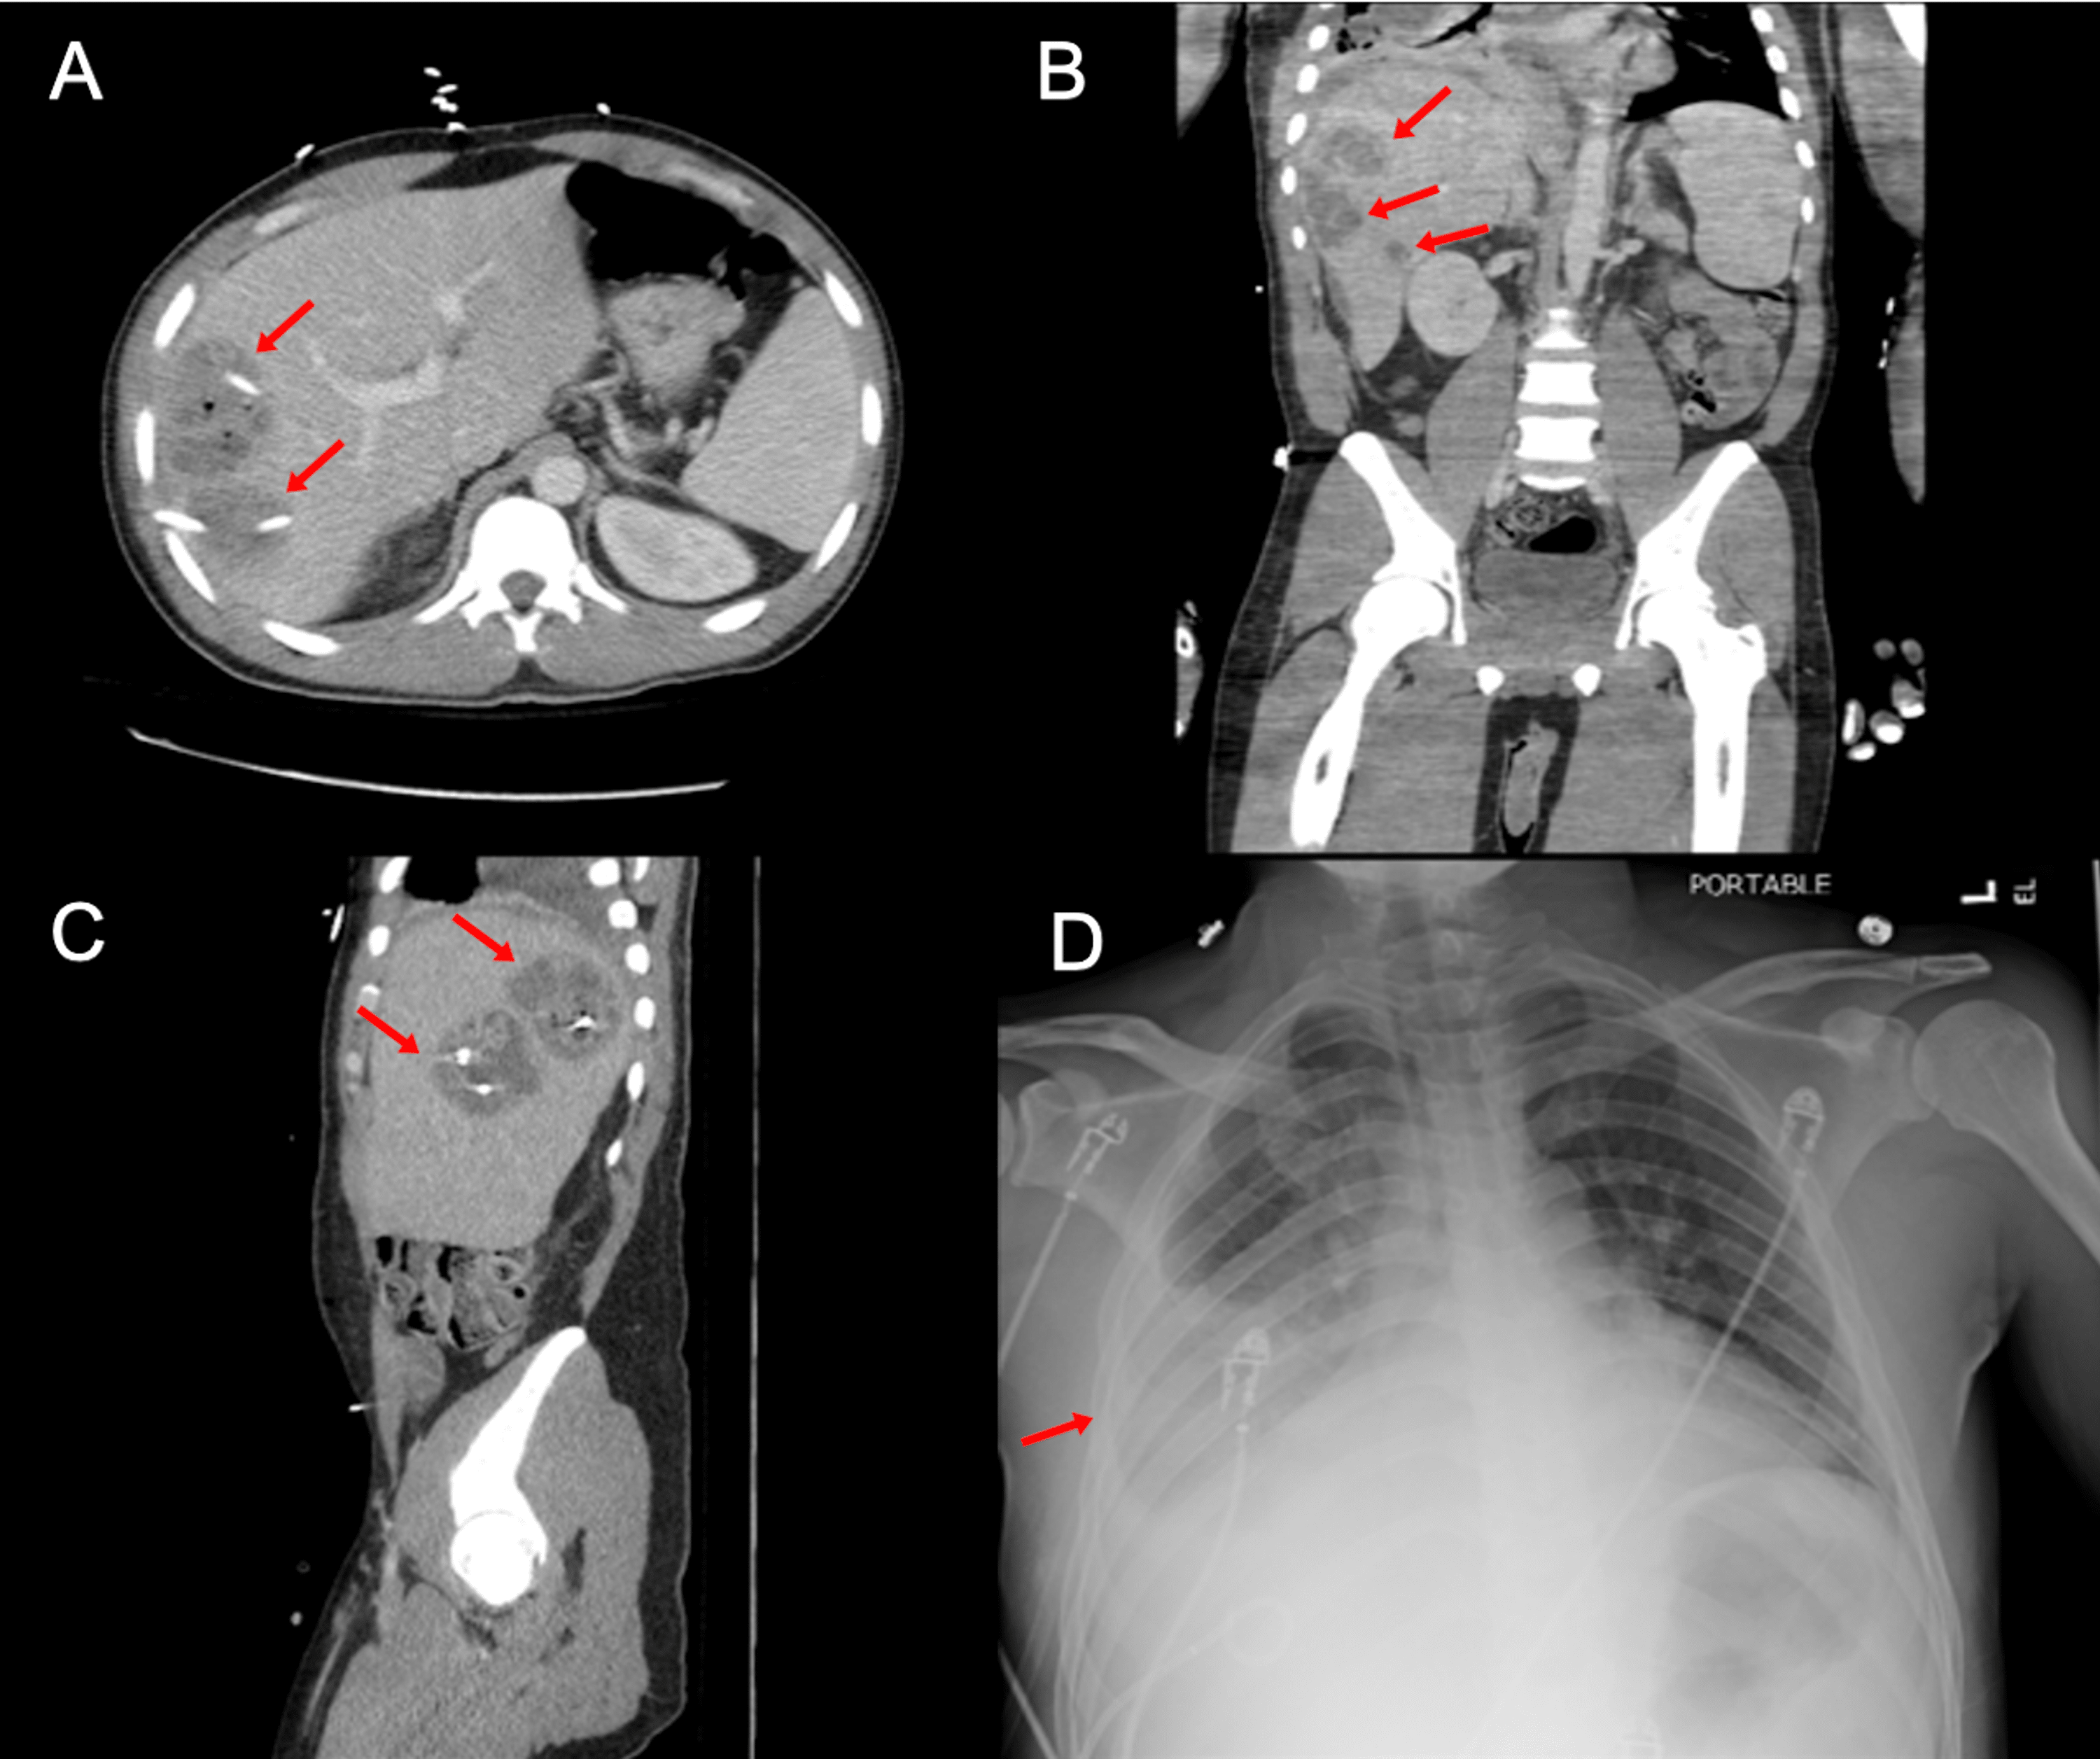

Cureus Liver in the Chest A Case of a Large Traumatic Diaphragmatic Chest X Ray For Liver Organ enlargement can sometimes be seen as a big liver or spleen. It occurs when fluid builds up in the. Mri also shows blood flow and therefore complements doppler. They can also show ongoing lung conditions, such. Mri is superior to ct and ultrasonography for diagnosing diffuse liver disorders (eg, fatty liver, hemochromatosis) and for clarifying focal defects (eg, liver. Chest X Ray For Liver.